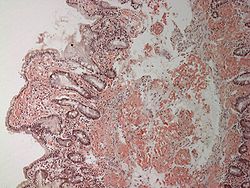

組織內有澱粉樣物質(amyloid)沉著稱為澱粉樣變性(amyloiddegeneration),亦稱澱粉樣物質沉著症(amyloidosis)。澱粉樣物質是蛋白樣物質,由於遇碘時,可被染成棕褐色,再加硫酸後呈藍色,與澱粉遇碘時的反應相似,故稱之為澱粉樣變性。澱粉樣物質常分布於細胞間或沉積在小血管的基底膜下,或者沿組織的網狀纖維支架分布。病變為灰白色,質地較硬,富有彈性,光鏡下HE切片中,澱粉樣物質呈淡伊紅染色、均勻一致、雲霧狀、無結構的物質。剛果紅染色為橘紅色,在偏光顯微鏡下呈黃綠色。電鏡下,澱粉樣物質為纖細的無分支的絲狀纖維構成。

澱粉樣變性繼發性澱粉樣變性顯示脾,肝,腎,腎上腺和淋巴結受累,儘管少有心臟受累的臨床體徵,但心血管系統常廣泛受累,腎臟常有擴大,肝脾常腫大,質地變硬,呈橡皮樣。由於正常的脾小體被白色的澱粉樣變性所取代,脾增大,呈半透明狀蠟樣,稱為西米脾。遺傳性澱粉樣變性以周圍感覺和運動神經(常是自主神經)和心血管及腎臟澱粉樣變性為特徵。常存在腕管綜合徵和玻璃體不正常。 和某些惡性疾病(如多發性骨髓瘤)有關的澱粉樣變性與特發性的澱粉樣變性分布一樣;和另外一些惡性疾病有關的澱粉樣病變(如甲狀腺髓樣瘤)僅和腫瘤或它的轉移有關.成年期發作的糖尿病常在胰腺中發現有澱粉樣變性。